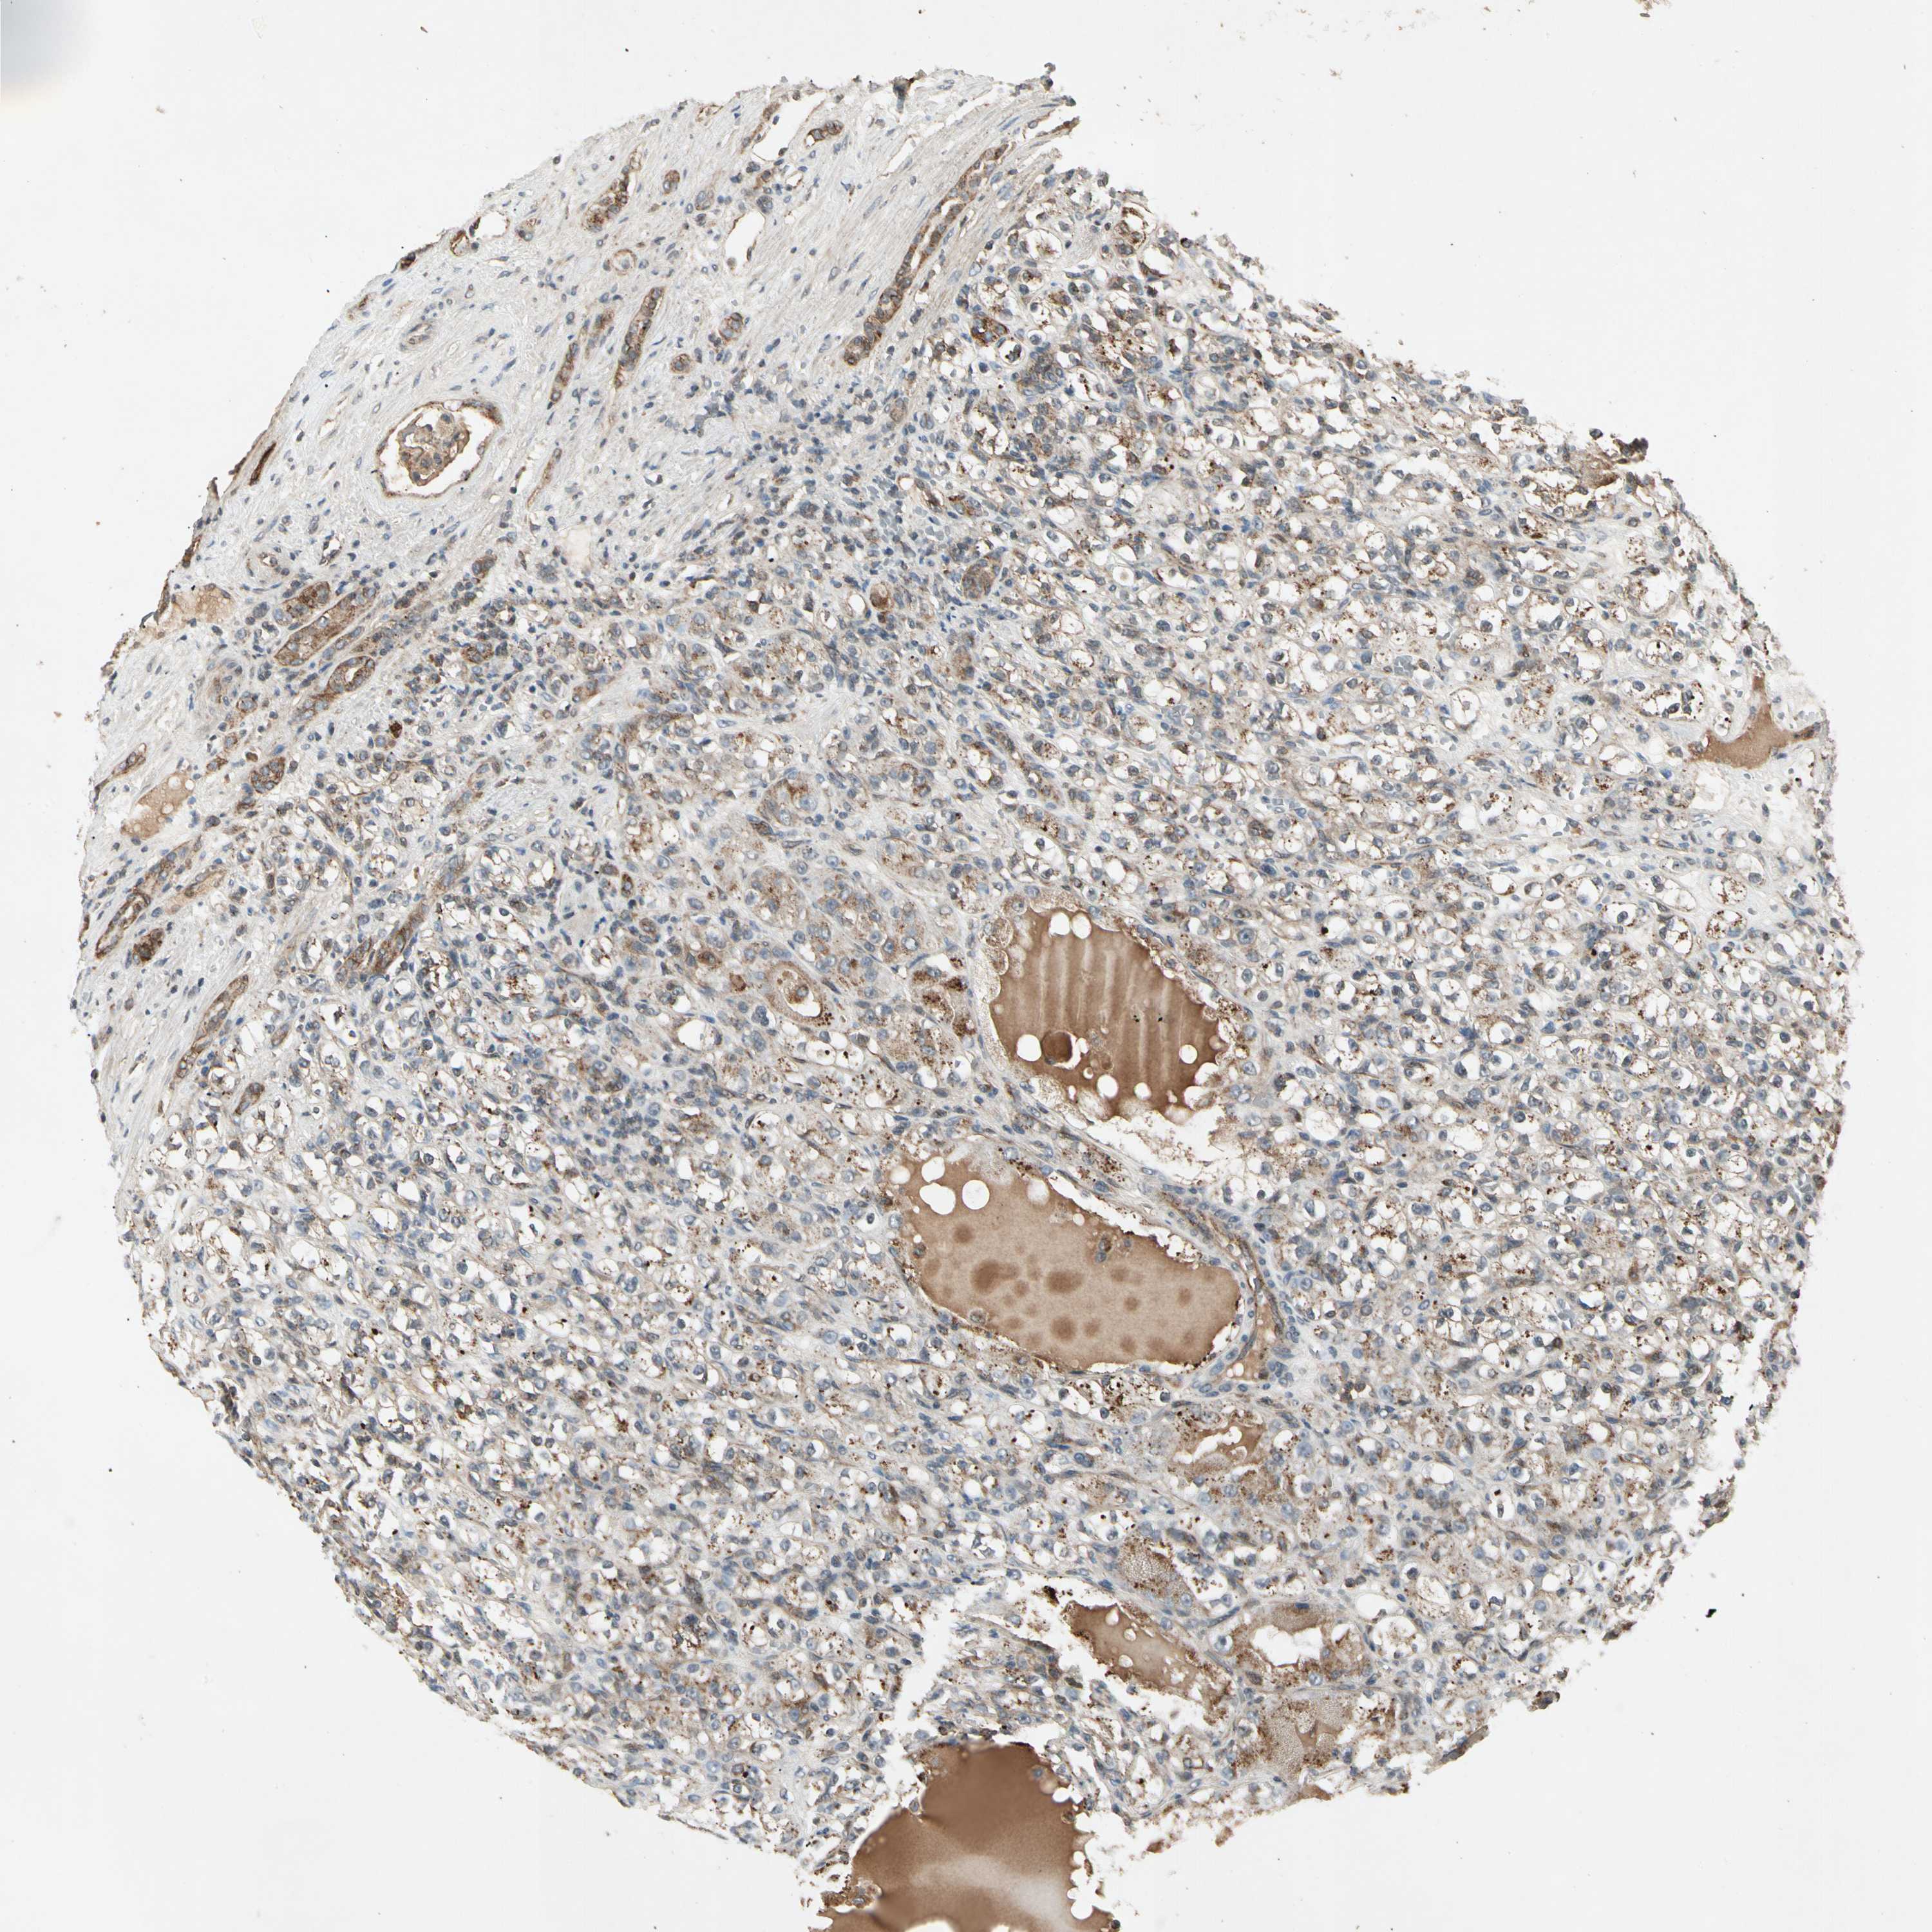

KIDNEY RENAL CLEAR CELL CARCINOMA (VALIDATION) - Interactive survival scatter ploti

The Survival Scatter plot shows the clinical status (i.e. dead or alive) for all individuals in the patient cohort, based on the same data that underlies the corresponding Kaplan-Meier plots. Patients that are alive at last time for follow-up are shown in blue and patients who have died during the study are shown in red.

The x-axis shows the expression levels (FPKM) of the investigated gene in the tumor tissue at the time of diagnosis. The y-axis shows the follow-up time after diagnosis (years). Both axes are complimented with kernel density curves demonstrating the data density over the axes. The top density plot shows the expression levels (FPKM) distribution among dead (red) and alive patients (blue). The right density plot shows the data density of the survived years of dead patients with high and low expression levels respectively, stratified using the cutoff indicated by the vertical dashed line through the Survival Scatter plot. This cutoff is automatically defined based on the FPKM cutoff that minimizes the p-score. The cutoff can be changed by dragging the vertical line or by entering a cutoff value in the square labeled "Current cut-off".

Under the Survival Scatter plot the p-score landscape (black curve; left axis) is shown together with dead median separation (red curve; right axis). Dead median separation is the difference in median mRNA expression between patients who have died with high and low expression, respectively. It is calculated as follows: median FPKM expression of dead patients with high expression - median FPKM expression of dead patients with low expression. This is intended to aid the user in visually exploring custom cutoffs and the associated p-scores and dead median separation.

Individual patient data is displayed and can be filtered by clicking on one or more of the category buttons on the top of the page. Categories describing expression level and patient information include: high, low, alive, dead, female, male and tumor stages. The scale of the x-axis can be toggled between linear and log-scale by clicking on the "x log" button. Mouse-over function shows TCGA ID, patient information and mRNA expression (FPKM) for each patient.

& Survival analysisi

Kaplan-Meier plots summarize results from analysis of correlation between mRNA expression level and patient survival. Patients were divided based on level of expression into one of the two groups "low" (under cut off) or "high" (over cut off). X-axis shows time for survival (years) and y-axis shows the probability of survival, where 1.0 corresponds to 100 percent.

FLOT1 is not prognostic in Kidney Renal Clear Cell Carcinoma (validation)

Best expression cut offi

Based on the FPKM value of each gene, patients were classified into two groups and association between prognosis (survival) and gene expression (FPKM) was examined. The best expression cut-off refers the FPKM value that yields maximal difference with regard to survival between the two groups at the lowest log-rank P-value. Best expression cut-off was selected based on survival analysis .

When clicking on this number, the vertical dashed line indicating cut-off, the interactive survival plot, and the Kaplan-Meier curve will be adjusted to show results based on the best expression cut-off.

: 49.61

TCGA RNA samplesi

RNA-seq data is reported as average FPKM (number Fragments Per Kilobase of exon per Million reads), generated by the The Cancer Genome Atlas (TCGA) .

Normal distribution across the dataset is visualized with box plots, shown as median and 25th and 75th percentiles. Points are displayed as outliers if they are above or below 1.5 times the interquartile range. FPKM values of the individual samples are presented next to the box plot.

Average pTPM 40.4

Number of samples 100